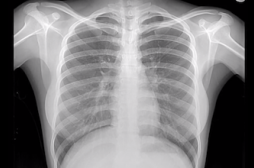

LES MALADIES

J'AI MAL

J ai Mal Bras et mains Bras et mains Tête et cou Torse et haut du dos Jambes et pied